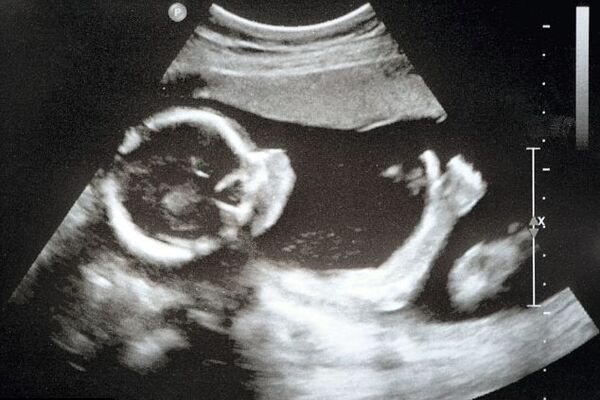

Bebekler anne karnında ne yapar?